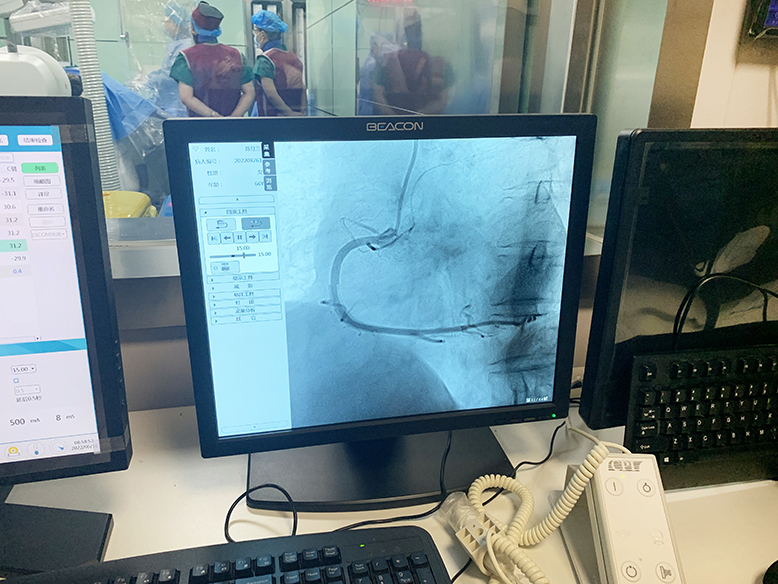

2022年6月16日,濱海新仁慈醫(yī)院在鄭州大學(xué)介入治療研究所的技術(shù)支持下,成功實施了兩例冠狀動脈造影術(shù)(DSA),標(biāo)志著該院在心血管疾病的治療上邁上了新臺階。

經(jīng)術(shù)前充分準(zhǔn)備,上午8時手術(shù)順利開始。介入導(dǎo)管室內(nèi),兩位醫(yī)師緊張有序地操作,術(shù)中患者情況穩(wěn)定。上午9時許,在鄭州大學(xué)第二附屬醫(yī)院專家和濱海新仁慈醫(yī)院介入導(dǎo)管室團(tuán)隊的不懈努力下,手術(shù)順利完成。術(shù)后,患者無任何不良癥狀,安返病房。

據(jù)濱海新仁慈醫(yī)院介入導(dǎo)管室主任辛達(dá)路介紹,冠狀動脈造影術(shù)是診斷冠心病的“金標(biāo)準(zhǔn)”。通過冠狀動脈造影,可以了解冠狀動脈血管分布,發(fā)現(xiàn)冠狀動脈是否有狹窄以及血管狹窄程度。根據(jù)冠狀動脈造影結(jié)果,決定是否對狹窄血管進(jìn)行支架置入術(shù)或者冠狀動脈搭橋手術(shù)治療。